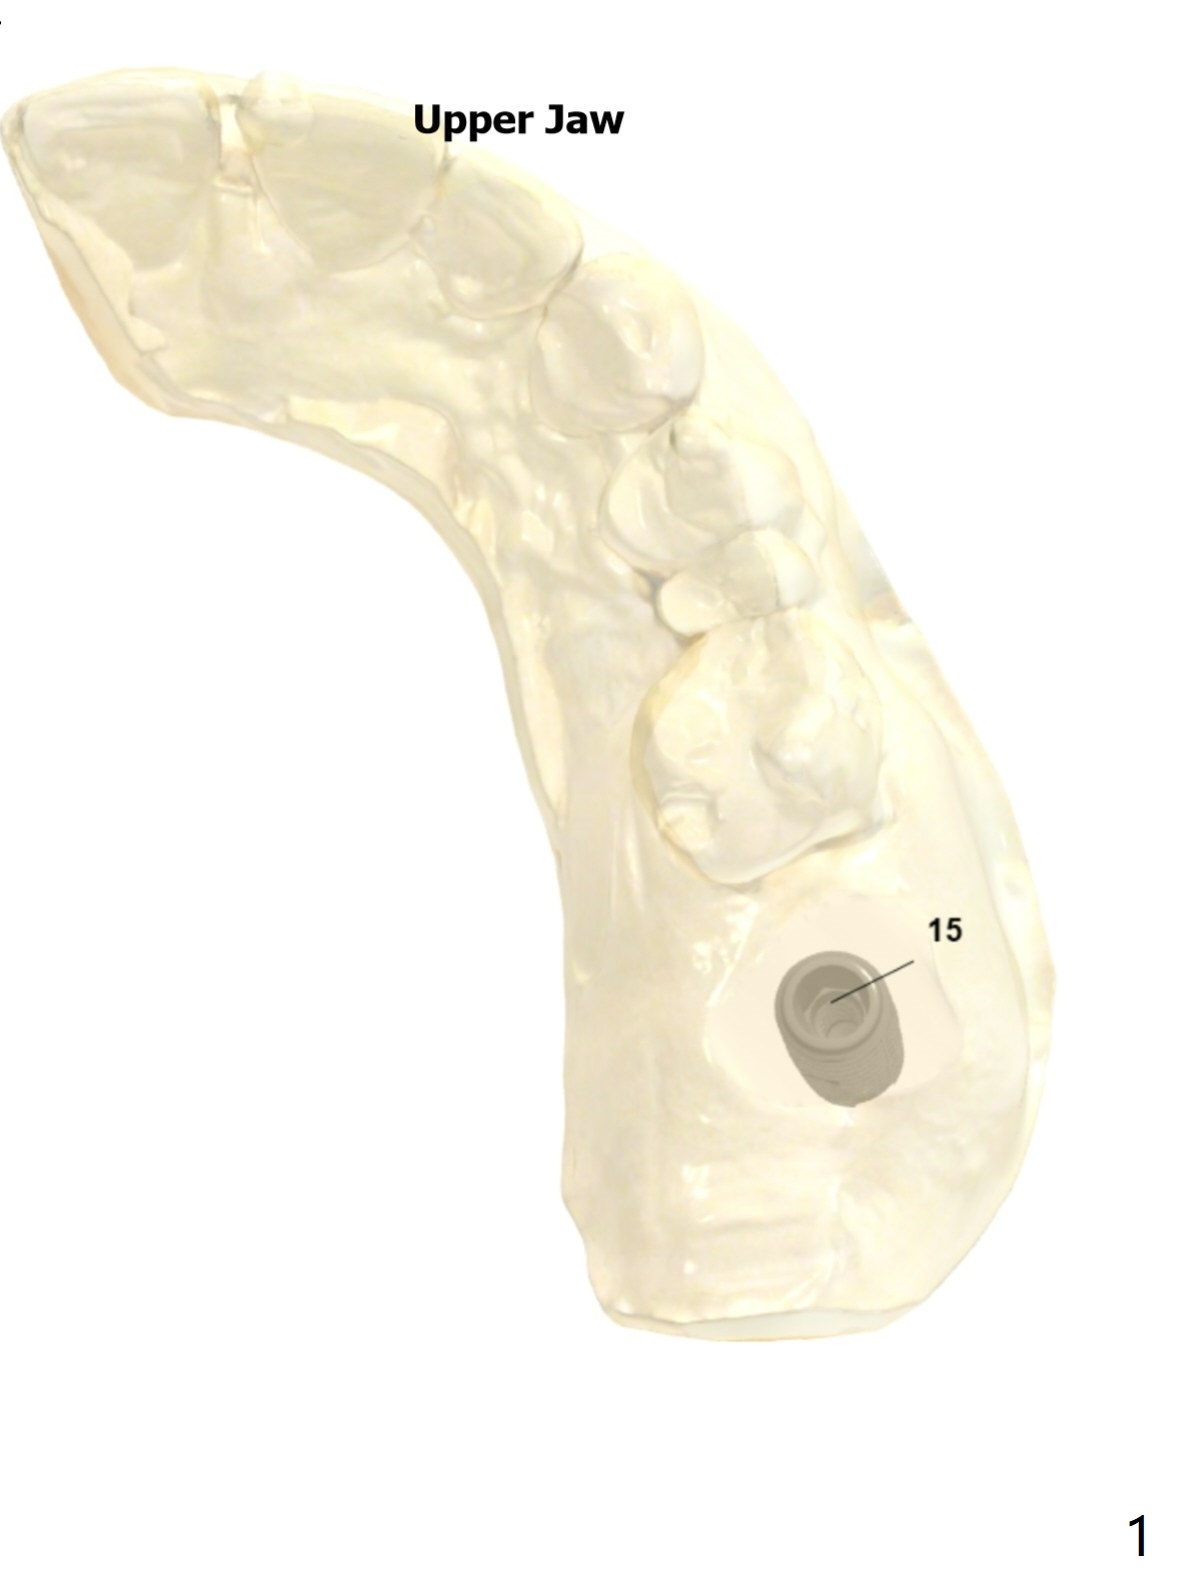

Limited Apical Bone-Sinus Lift

Return to Upper Molar Immediate Implant, Trajectory II, Clindamycin